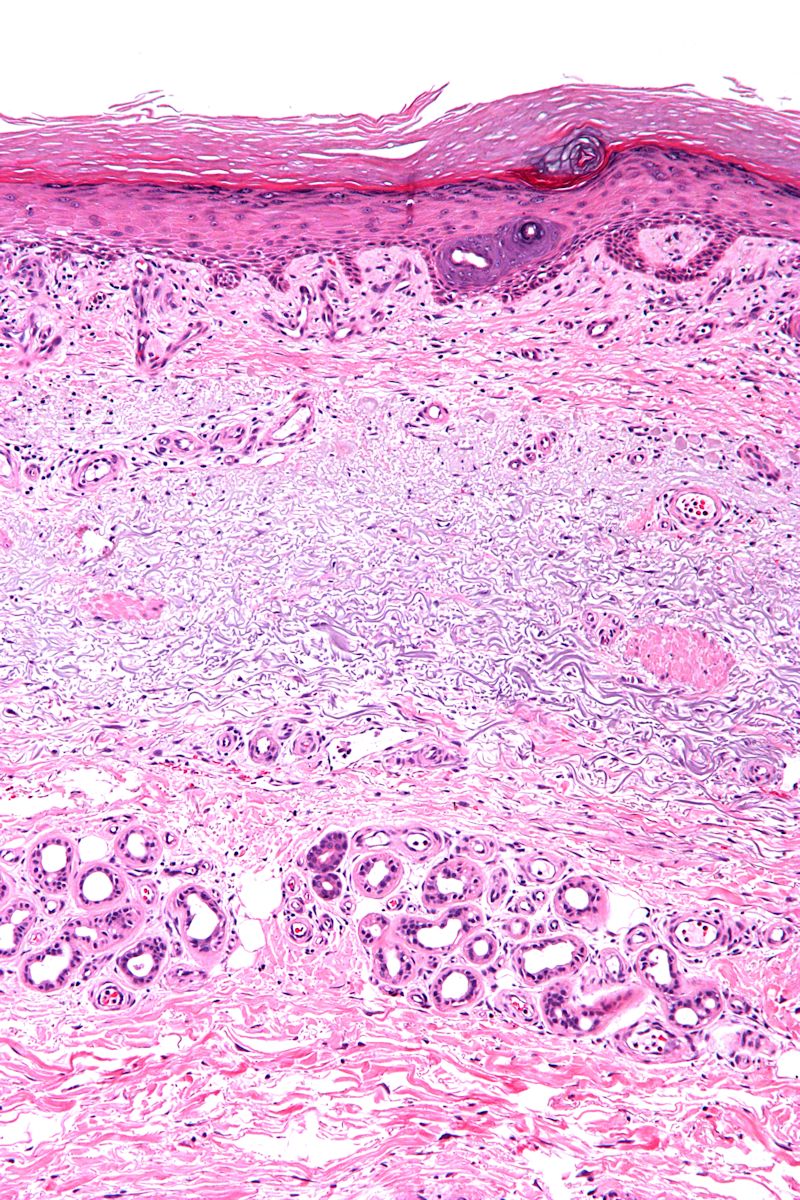

elastosis is ook een PA term, de degeneratie van het collageen en de elastine

vezels is ook histologisch zichtbaar: vaak is er een blauwgrijze (basofiele)

verkleuring hoog in de dermis.

![Solaire elastosis (click on photo to enlarge) [source: Michael Bonert (Nephron) - Wikimedia - Creative Commons License 3.0] Solaire elastosis](../../../images/solaire-elastosis-1z.jpg) |

![Solaire elastosis (click on photo to enlarge) [source: Michael Bonert (Nephron) - Wikimedia - Creative Commons License 3.0] Solaire elastosis](../../../images/solaire-elastosis-2z.jpg) |